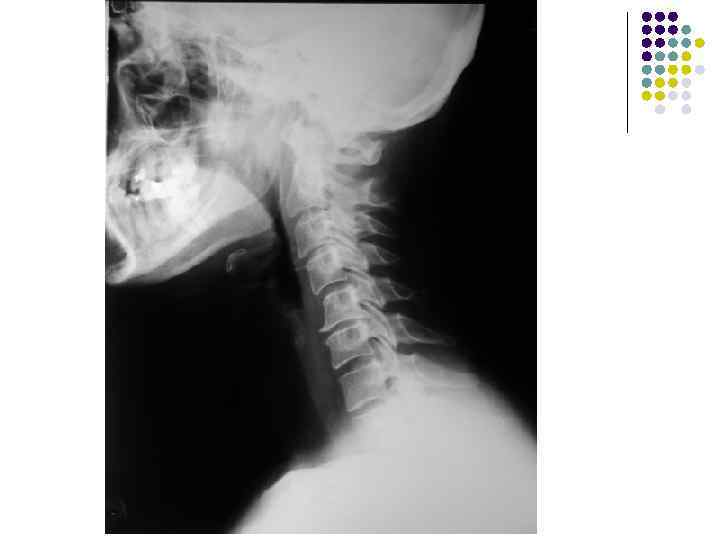

l l l На рентгенограмме шейного отдела позвоночного столба в боковой проекции определяется: выраженные распространенные дистрофические изменения в виде остеохондроза и артроза дугоотростчатых суставов: неравномерное сужение межпозвонковых пространств, субхондральный остеосклероз, костные разрастания по краям тел позвонков, сужение рентгеновских суставных щелей дугоотостчатых суставов с субхондральным остеосклерозом и небольшими костными разрастаниями по краям суставных поверхностей. Наиболее ярко эти изменения выражены в сегментах С 5 -6 -7 Признаки ограниченного смещения тел позвонков в виде симптома «распорки» и кифотической установки. Заключение: Остеохондроз шейного отдела позвоночного столба. Артроз дугоотростчатых суставов. Деформация шейного отдела позвоночника с нарушением статики.

1.

l l l На рентгенограмме шейного отдела позвоночного столба в боковой проекции определяется: выраженные дистрофические изменения за счет остеохондроза - значительное, неравномерное сужение межпозвонковых пространств с нарушением их правильной клиновидной формы, выраженный субхондральный остеосклероз, значительные костные разрастания по передним краям тел позвонков. Наиболее ярко эти изменения представлены в сегментах С-5, 6, 7. Помимо этого, в этих же сегментах фиксируются дистрофические изменения дугоотростчатых суставов – сужение рентгеновских суставных щелей, субхондральный остеосклероз и костные разрастания по краям суставных поверхностей. Выпрямление физиологического лордоза. Признаки системного нарушения статики тел позвонков в виде симптомов кифотической установки. Деструктивных изменений нет Заключение: Комплекс дистрофических изменений шейного отдела позвоночного столба в виде остеохондроза и артроза дугоотростчатых суставов с преимущественными проявлениями в нижних сегментах отдела. Нарушение статики тел позвонков

3.

l На рентгенограмме шейного отдела позвоночного столба в боковой проекции определяется: выраженные дистрофические изменения за счет остеохондроза с преимущественными проявлениями в сегменте С 5 -6 – сужение и деформация межпозвонковых пространств, выраженный субхондральный остеосклероз, значительные костные разрастания по краям тел позвонков. Выпрямление физиологического лордоза. Признаки нарушения положения тела С 4 (симптом «распорки» )